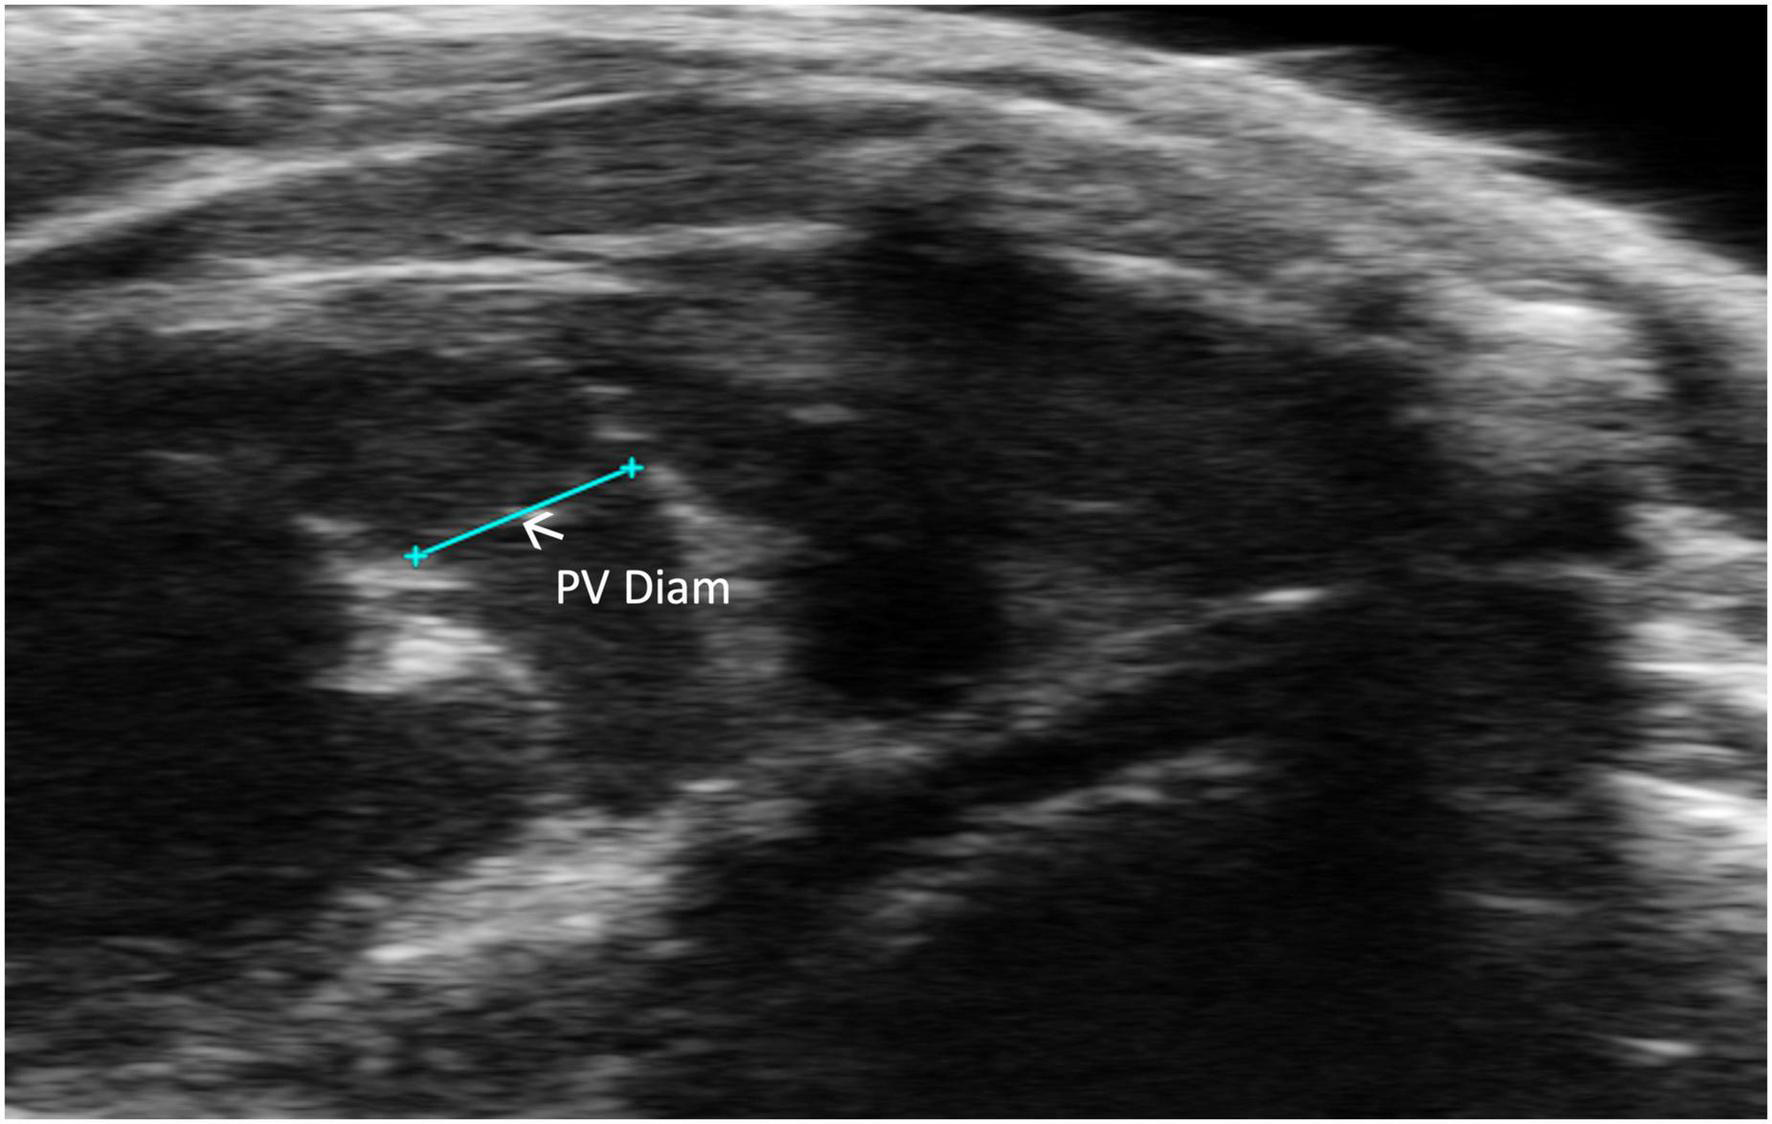

2.2.2.3 Pulmonic valve diameter

Pulmonic valve diameter (PV diameter) measures, in millimeters, the length of the pulmonic valve. This measurement can be performed using a PLAX or PSAX view of the pulmonic valve; however, visualization is typically easier in PLAX (Figure 7). PV diameter can be used to assess whether pulmonic valve stenosis or dilation is present. The PV diameter can also be used with PV VTI to calculate PV SV and CO.

FIGURE 7

Pulmonic valve (PV) diameter is acquired and analyzed in B-mode of the parasternal long axis (PLAX) view.